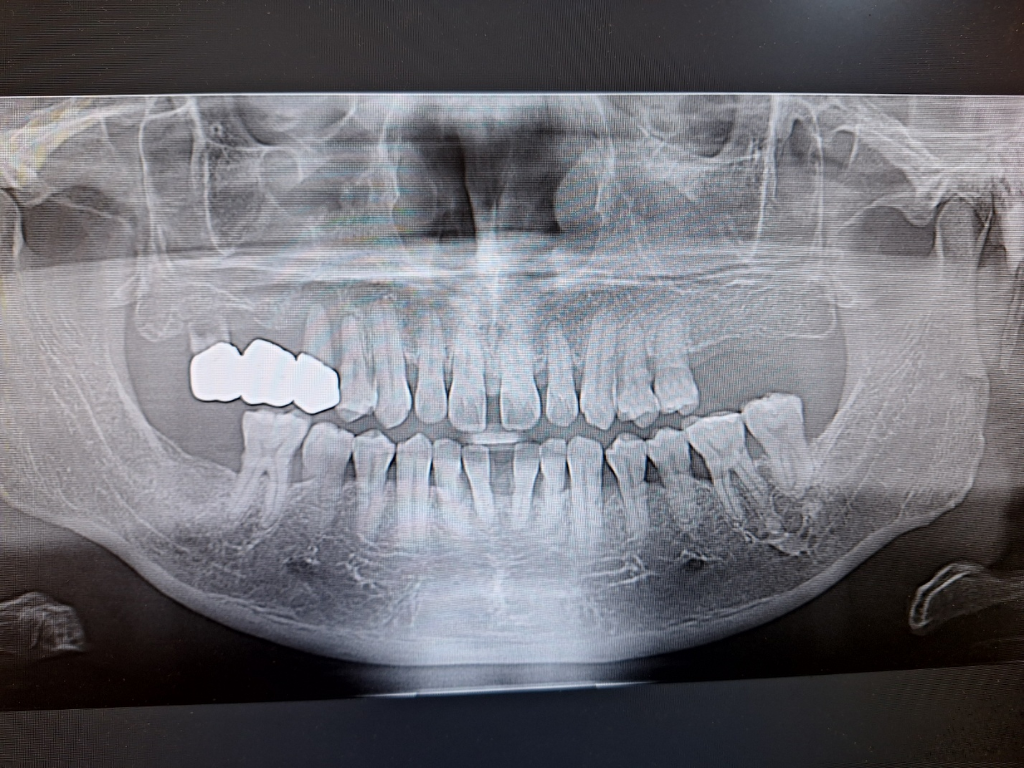

임플란트를 빨리 하시는 것이 좋겠습니다. 잇몸상태도 그렇고 반대측 치아에도 문제가 생길 수 있습니다.

일단은 발치를 하시고 나서 3-6개월정도 기다려 보시고 잇몸뼈가 어느정도 차오르면 그냥 하셔도 되지만, 염증이 심해서 잇몸뼈가 차오르지 앟는다면 상악동 거상술과 뼈이식을 하셔야될수도 있습니다.

치아를 상실하게 되면 해당 부위에 주변치아가 이동할 수 있고 치아에 가해질 힘이 다른 치아에 무리를 줄 수 있기 때문에 가능한 빠른 시일내에 치료를 하는 것이 좋습니다.

통상적으로 발치 후 2년 이상 지체되면 잇몸과 잇몸뼈가 수축되어 임플란트를 심기 더 어렵습니다 또한 14번 치아도 상태가 좋아보이진 않습니다